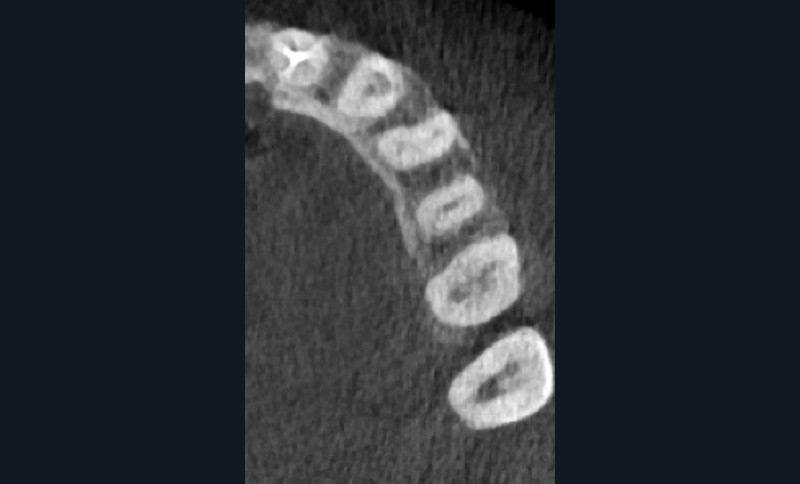

Si l’étude de Peters [18] nous montre que l’instrumentation laisse 35 % du volume canalaire non instrumenté, Ricucci et Siqueira montrent que la préparation physico-chimique n’élimine que partiellement les tissus nécrotiques à l’entrée des canaux latéraux, des isthmes et des ramifications apicales, en laissant des tissus enflammés et infectés, en association avec des lésions apicales [29] (fig. 4 et 5).

Fig. 4 – Coupe d’une racine mésiale de molaire mandibulaire avec deux canaux traités. Coupe à 3 mm de l’apex, coloration Brown et Brenn, technique modifiée par Taylor. Ces images montrent un isthme étroit avec une infection bactérienne, ce qui prouve l’importance de désinfecter et d’inclure l’isthme dans les traitements conventionnels et dans les rétropréparations apicales en chirurgie endodontique.

L’hypochlorite de sodium, communément utilisé comme irrigant pour ses propriétés antibactériennes et solvantes, se doit d’être véhiculé pour atteindre ces zones retranchées [30]. Le laser Erbium permettra d’activer localement cette solution, augmentant la densité énergétique au sein de la zone ciblée, et donc de la véhiculer. Cette solution activée par le laser se fera à un faible niveau d’énergie avec des pulses courts, afin de rester dans un mode subablatif, et de permettre la formation d’une onde de choc initiatrice d’un phénomène photo-acoustique. Ceci tout en évitant tout risque de dégradation des parois dentinaires, d’échauffement, et de dommages thermiques [31].